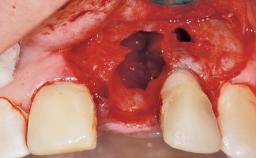

Immediate Flapless Placement of an Implant in a Maxillary Left Central Incisor Site

A 42-year-old female patient was referred to our clinic at the School of Dentistry of the University of São Paulo in November 2004, presenting a deficient restoration in the upper left central incisor. The clinical examination revealed no gingival retraction or any signs of gingival inflammation and, therefore, previous periodontal treatment was not considered. The patient presented a high lip line at full smile and a thin tissue biotype. This combination characterized a high-risk situation from an anatomic point of view, which required careful preoperative planning and cautious surgical execution.

Placement Protocol Immediate implant placement

Socket Morphology Single-root socket

Socket Integrity Sufficient, with intact bone walls